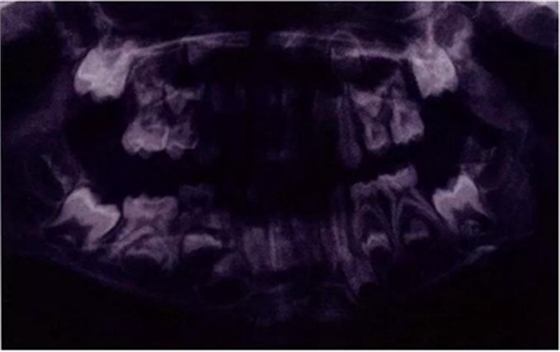

圖8展示了一張5歲孩子右下第二乳磨牙嚴(yán)重下沉的口內(nèi)像。臨床檢查可見(jiàn)右下第一乳磨牙遠(yuǎn)中傾斜,朝向下沉乳牙。X線片檢查顯示所有恒牙胚都存在(圖9)。無(wú)論是臨床還是影像學(xué),都可檢查到有齲齒的存在。鑒于這顆下沉乳牙在年齡較小時(shí)就已經(jīng)非常嚴(yán)重,同時(shí)還患有齲病,因此決定予以拔除。后期在放置間隙保持器的同時(shí)還應(yīng)持續(xù)觀察監(jiān)測(cè)右下第一恒磨牙和第二前磨牙的萌出情況。

圖9:一名五歲患兒右側(cè)下頜第二乳磨牙嚴(yán)重下沉的曲面體層片